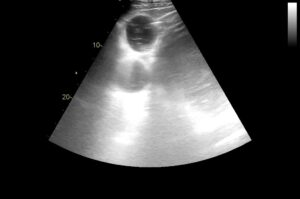

Echocardiogram of the heart is important to assess the chambers and valves of the heart and is invaluable in the assessment of the significance of many types of heart murmur.

Colour flow Doppler is used to assess dynamic blood flow through different parts of the heart.

Ultrasonographic examination of the intestines and other abdominal structures (eg. liver, kidney and spleen) is an important diagnostic tool in the investigation of horses with colic, weight loss or diarrhoea.

Ultrasound guidance is frequently used to allow safe and precise biopsy of internal structures such as the liver, lungs and kidneys.